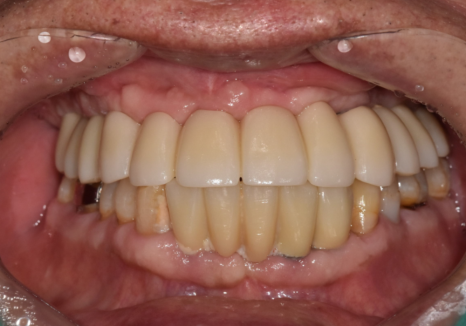

8개월의 여정, 다시 찾은 일상

70대 당뇨 환자분의

상악 무치악 치료는 총 8개월이 걸렸습니다.

현재 환자분은 6개의 임플란트로

편안하게 식사를 하고 계십니다.

250308 (전) 251020 (후)